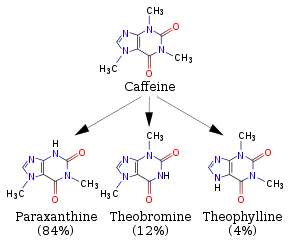

Caffeine is metabolized in the liver by the cytochrome P450 oxidase enzyme system, in particular, by the CYP1A2 isozyme, into three dimethylxanthines,[188] each of which has its own effects on the body:

- Paraxanthine (84%): Increases lipolysis, leading to elevated glycerol and free fatty acid levels in blood plasma.

- Theobromine (12%): Dilates blood vessels and increases urine volume. Theobromine is also the principal alkaloid in the cocoa bean (chocolate).

- Theophylline (4%): Relaxes smooth muscles of the bronchi, and is used to treat asthma. The therapeutic dose of theophylline, however, is many times greater than the levels attained from caffeine metabolism.[47]

1,3,7-Trimethyluric acid is a minor caffeine metabolite.[9] 7-Methylxanthine is also a metabolite of caffeine.[189][190] Each of the above metabolites is further metabolized and then excreted in the urine. Caffeine can accumulate in individuals with severe liver disease, increasing its half-life.[191]